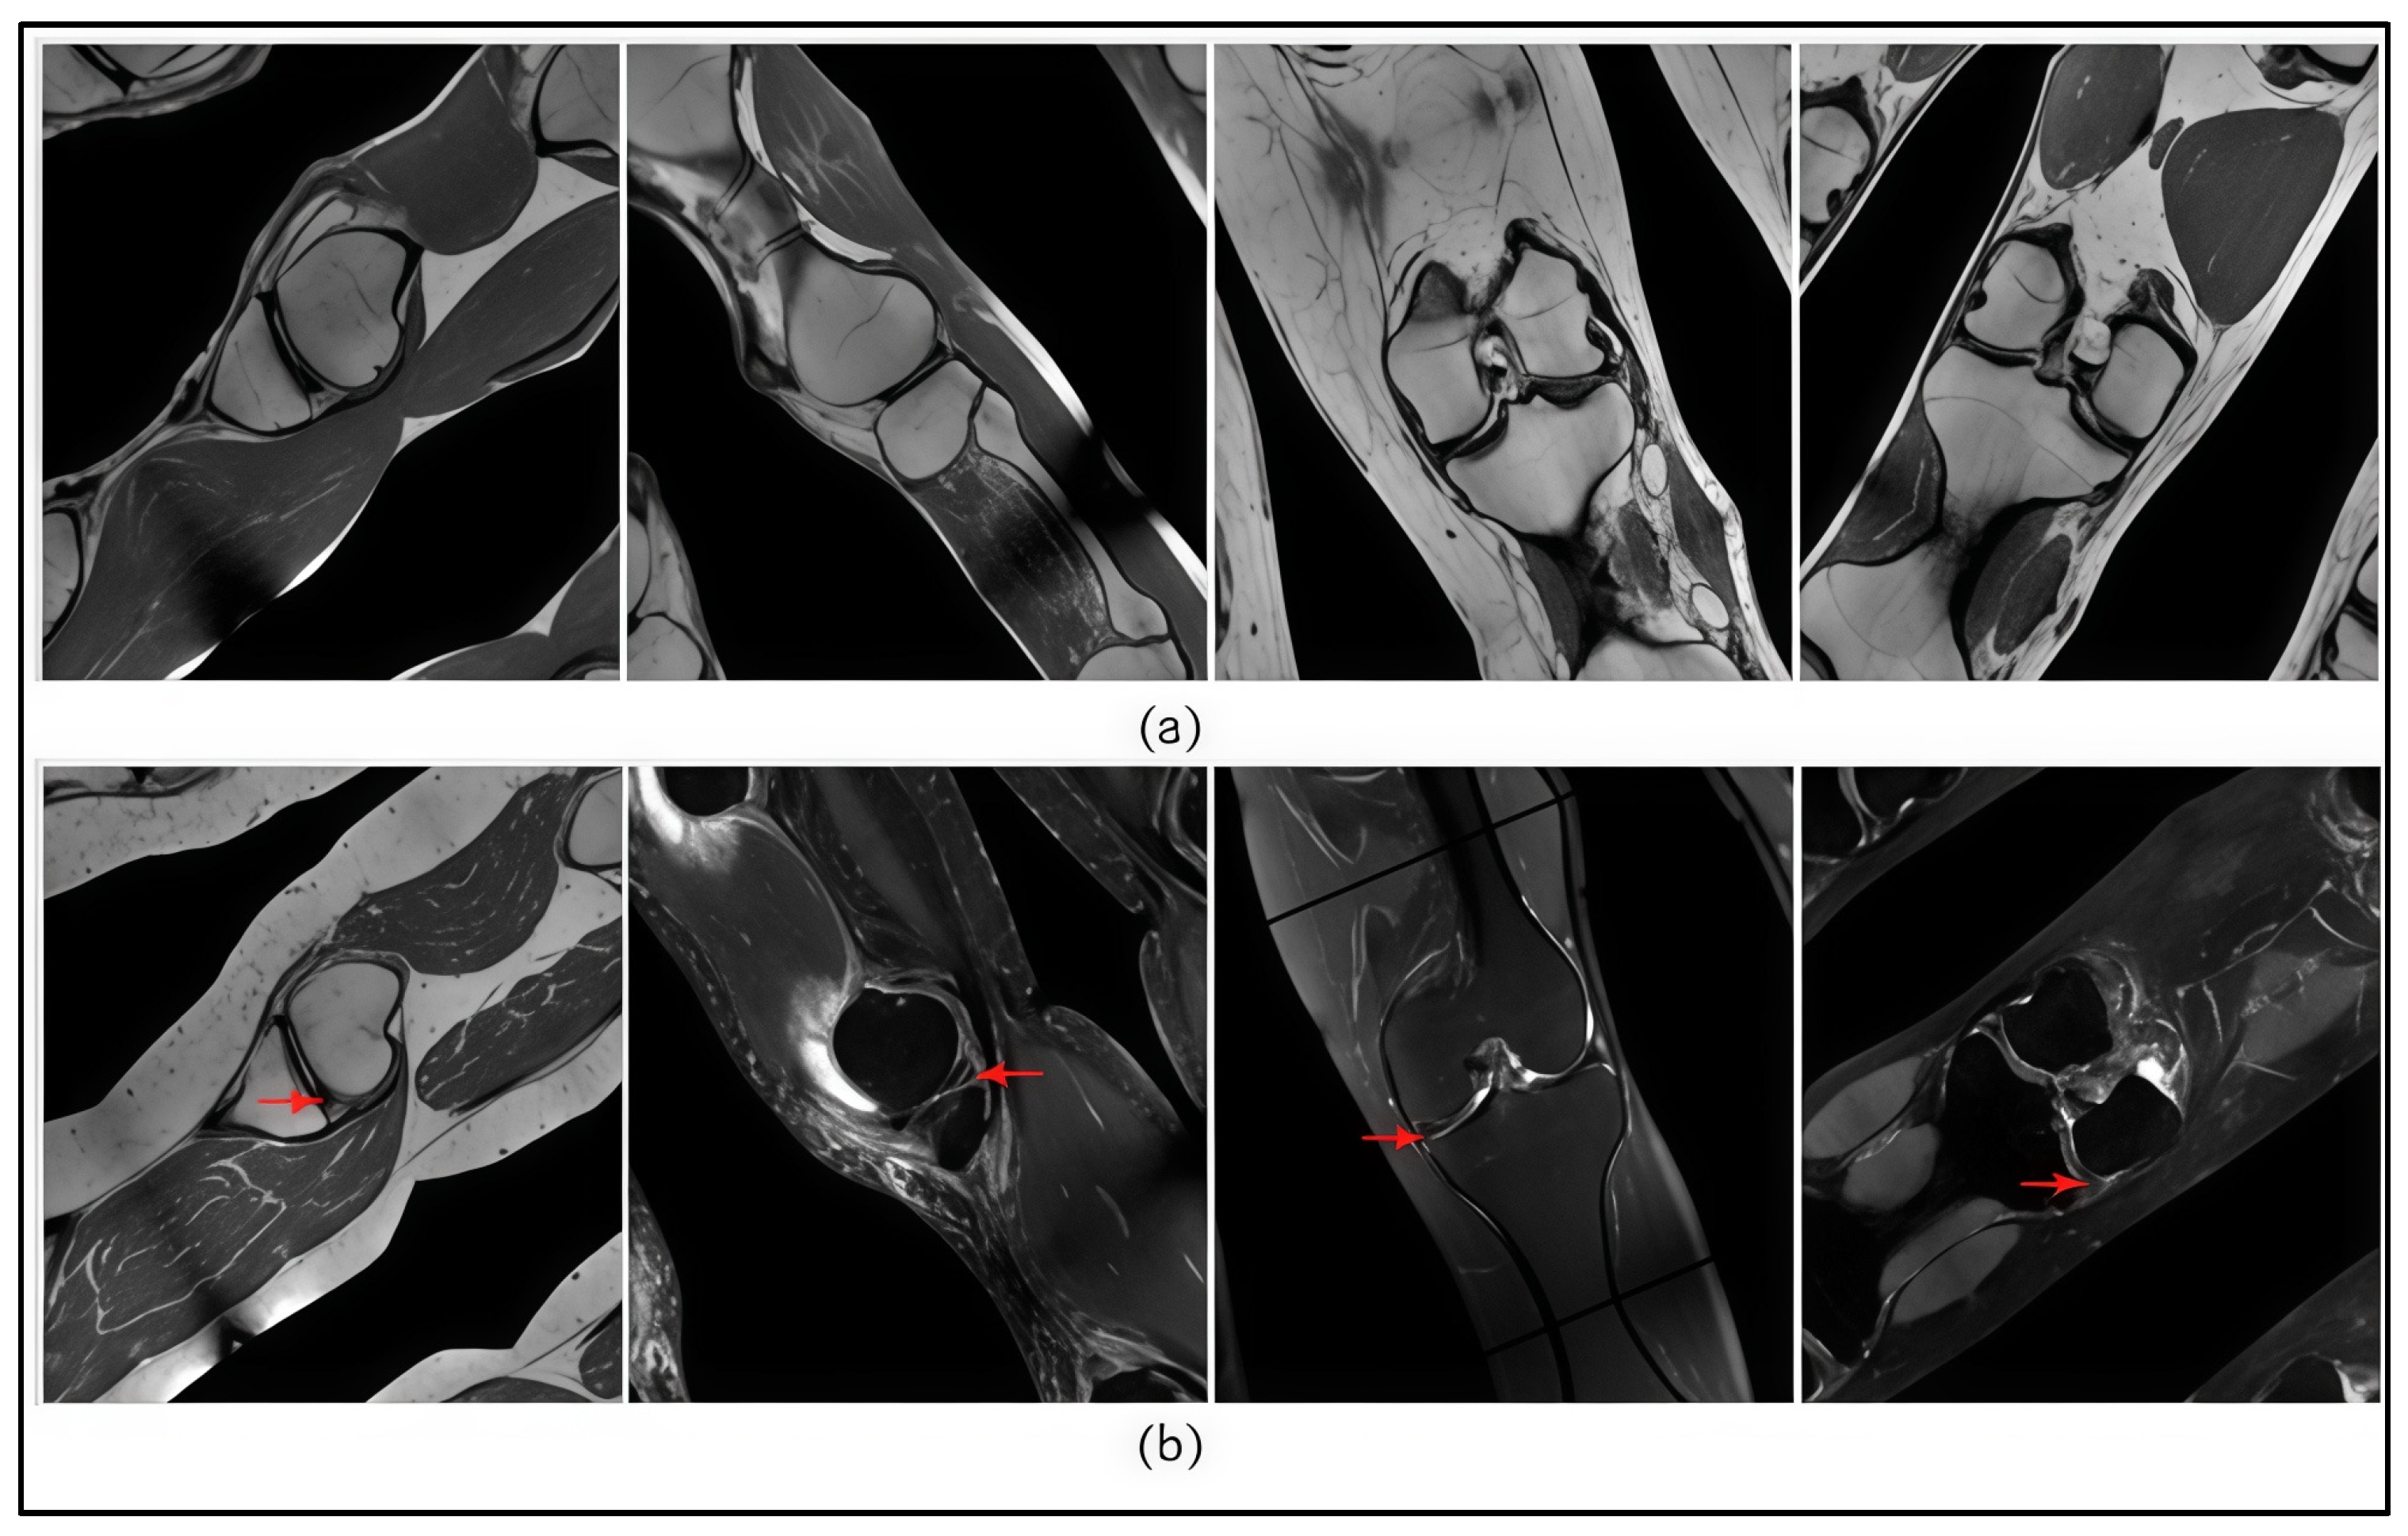

5.1. Analysis of Misclassification and False Detection

- Subtle or partial manifestations of pathology: In some cases, signs of meniscal tears were only faintly or partially expressed, which posed challenges for automated recognition and increased the likelihood of misclassification.

- Presence of artefacts and noise: Mechanical and software-induced artefacts, shadows, signal inhomogeneities, and occlusions by adjacent bony structures were present in some images. These factors elevated the risk of false positive detections.

- Anatomical variability and multiscale complexity: Substantial inter-patient variation in the size, shape, and positioning of the meniscus introduced additional complexity in generalization. This was particularly challenging given the limited number of training samples representing such diverse anatomical configurations.